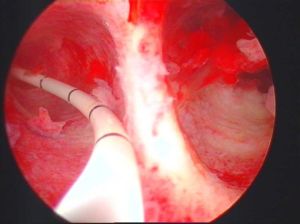

宮腔鏡檢查:宮腔鏡檢查是子宮縱隔診斷的標準,更直接準確的判斷子宮縱隔的類型。

宮腹腔鏡下冷剪刀分離法

會使子宮及腹壁留有瘢痕,創傷大,恢復時間長,甚至引起子宮粘連,對今後妊娠有一定影響,而且需避孕幾年才可懷孕,且多需剖宮分娩。宮腔鏡下冷器械和等離子電針

切開縱隔,而不要用電切環切除縱隔,那樣會導致瘢痕攣縮,無益擴大宮腔,在腹腔鏡監護下做更安全和準確,術後放入生物防黏膜。還有較大縱隔不要求一次到位,可以多次手術,切忌“矯枉過正”,那樣會造成宮底瘢痕過大,反而影響受孕。影響孕育